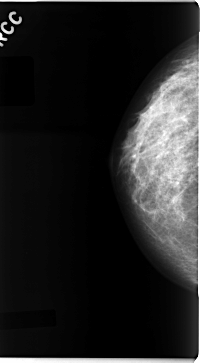

C_0090_1.LEFT_CC

LEFT_CC LINES 4720 PIXELS_PER_LINE 2416 BITS_PER_PIXEL 12 RESOLUTION 50 OVERLAY